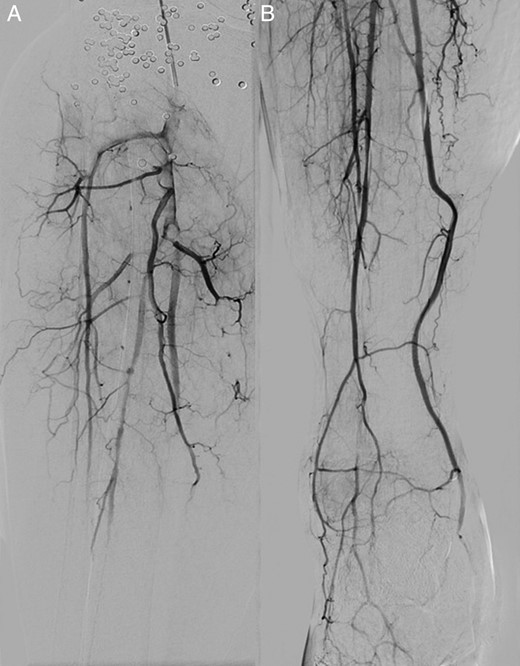

Angiography, via an antegrade right femoral approach, showed a false aneurysm of the popliteal artery at the knee joint level. There was occlusion of the calf vessels. A 6 mm × 25 mm Viabahn (Gore) covered stent was deployed to exclude the pseudoaneurysm, and a thrombolysis catheter was left in situ in the below-knee popliteal artery (Fig. 1). Thrombolysis was started using alteplase at a rate of 1 mg/h, with a concurrent infusion of heparin 400 IU/h via the arterial sheath, as per local protocol.

A digital subtraction angiogram of the right popliteal artery demonstrating the pseudoaneurysm, pre- (A) and post- (B) stenting. Note the numerous pellets in the soft tissues.